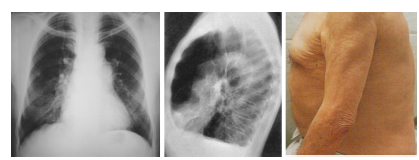

O enfisema é uma doença caracterizada pelo excesso de ar

na região pulmonar, estado que é consequência de um complexo

processo obstrutivo e destrutivo dos alvéolos e dos bronquíolos

terminais (ácino pulmonar) que acarreta a perda da elasticidade

pulmonar. Nos alvéolos, ocorre uma hiperdistensão com

dilatação excessiva, o que gera uma ruptura dos septos

alveolares. A distribuição e a abrangência da lesão variam em

cada caso. A seguinte imagem radiológica é típica de paciente

enfisematoso.